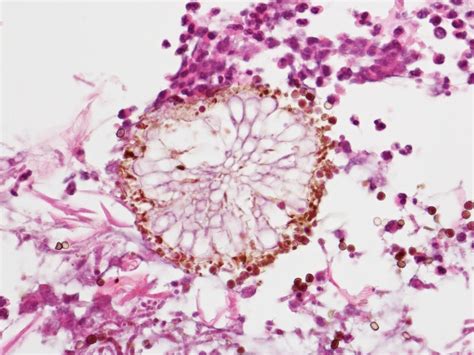

Aspergillosis is a type of fungal infection caused by Aspergillus, a common mold that lives everywhere in nature. Most of the time, Aspergillus is harmless. In fact, most people breathe in Aspergillus spores every day without getting sick. However, people with weakened immune systems may develop serious disease from Aspergillus infection.

Aspergillosis is an infection caused by Aspergillus, a common mold (a type of fungus) that lives indoors and outdoors. Most people breathe in Aspergillus spores every day without getting sick. However, people with weakened immune systems or lung diseases are at a higher risk of developing health problems due to Aspergillus.

Aspergillosis is an infection caused by a type of mold (fungus). The illnesses resulting from aspergillosis infection usually affect the respiratory system, but their signs and severity vary greatly. The mold that triggers the illnesses, aspergillus, is everywhere — indoors and outdoors.